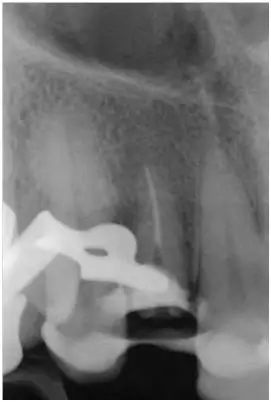

12至22牙的影像學(xué)檢查(圖5);

影像學(xué)檢查:根尖和根中三分一段內(nèi)的根管充填尚可(牙膠和根充糊劑),圓柱形根樁(鈦)位于根上三分之一段,在根中三分之一可見(jiàn)X線阻射性材料(粘結(jié)劑)。

根尖周無(wú)病理性變化

根長(zhǎng)度約15mm

圖5:外傷9天后的影像學(xué)檢查:12牙牙冠在釉牙骨質(zhì)界水平處折斷并且可以看到根管充填和一個(gè)折斷的鈦根樁。所有牙齒均顯示輕度的水平向骨吸收,根尖周未發(fā)現(xiàn)異常。11至22牙牙冠被修復(fù)過(guò)。